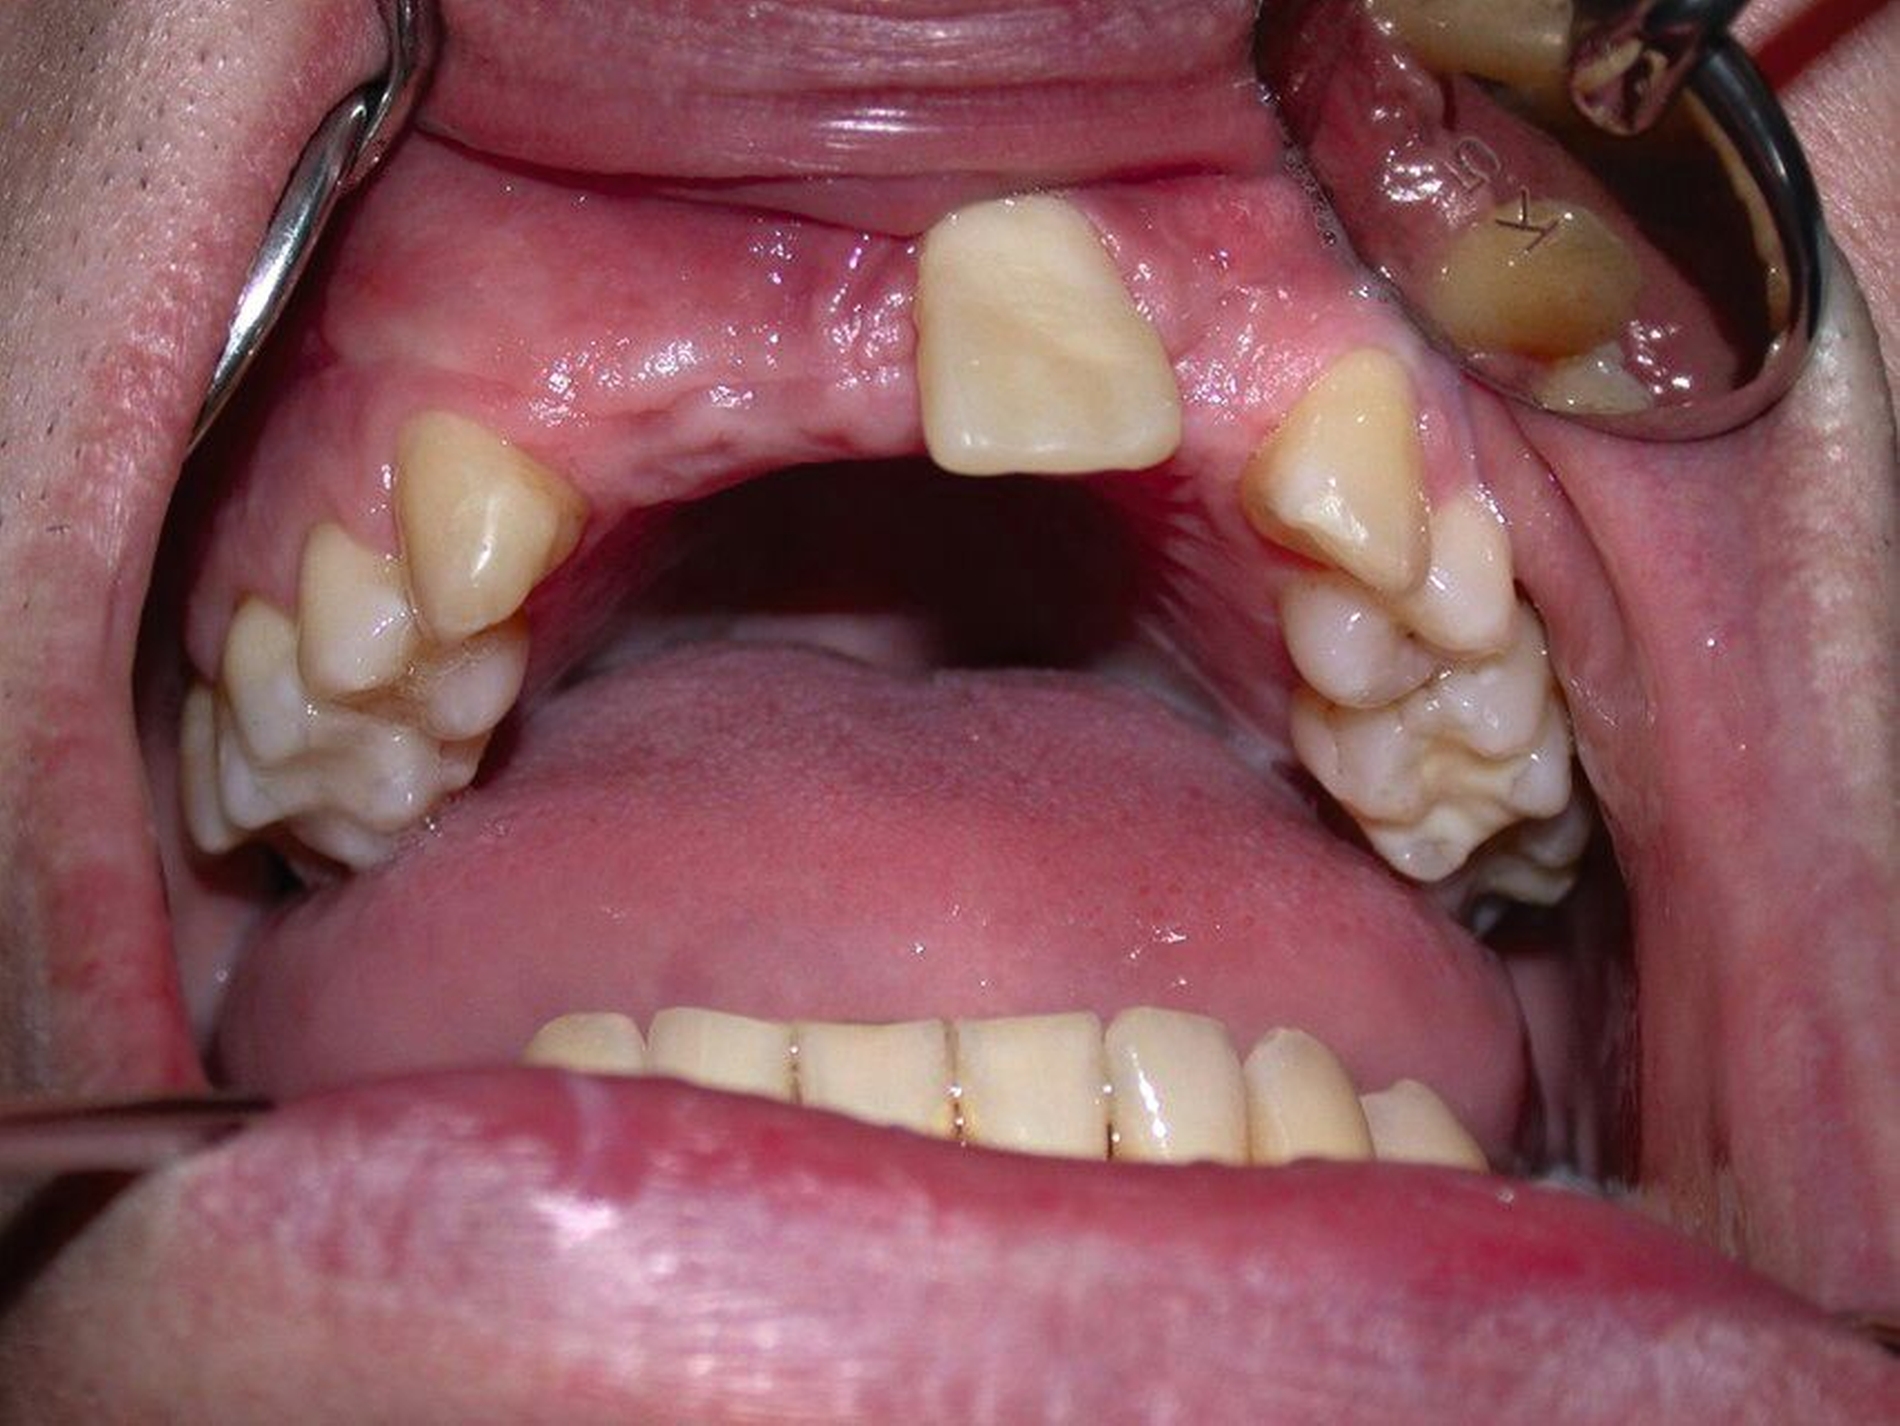

Der ankylosierte Zahn wird schonend gelöst („anluxiert“), bei Bedarf auch osteotomiert und aus seiner ursprünglichen Infraposition und/oder Verlagerung in die Okklusionsposition zum gesunden Nachbarzahn gestellt. Das Ziel dieser Maßnahme ist es, das vertikale Defizit durch die Ankylose-bedingte Wachstumshemmung aufzufangen (Abbildung 3). Je nach dem Zeitpunkt der Maßnahme und dem Verlauf kann der Zahn so vom frühen bis ins späte Wechselgebiss, in günstigen Fällen auch bis ins Erwachsenenalter, erhalten werden. Ob später ein kieferorthopädischer Lückenschluss, eine Prämolaren-Transplantation oder eine Implantation folgt, muss individuell nach der weiteren abzuschätzenden Prognose des Zahnes und nach dem Patientenwunsch entschieden werden.